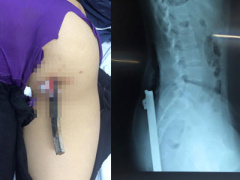

Nữ sinh bị thanh sắt trên xe ba bánh đâm xuyên người

Trên đường đi học về, nữ sinh đang đi xe đạp thì bất ngờ bị thanh sắt dài từ xe 3 bánh chở vật liệu xây dựng đâm phải.

01/11/2016 17:52:00